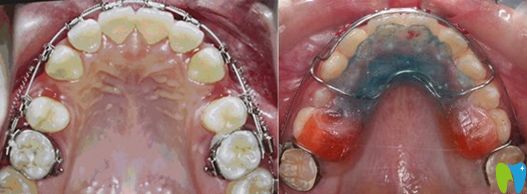

擴(kuò)弓矯正的前后效果對(duì)比圖